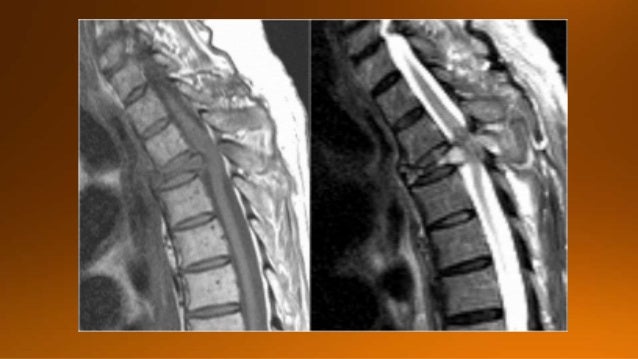

2. 2. In this presentation we will focus on spinal cord diseases that are characterized by high signal within the cord onT2WI. The most common causes are degenerative compressive myelopathy, inflammatory and demyelinating disorders.

3. 3. If we exclude myelopathy due to cord compression as seen in trauma, degeneration and metastatic disease, which is usually not a diagnostic dilemma, then the most common diseases of the spinal cord are Demyelinating diseases. AND Multiple Sclerosis is by far the most common demyelinating disease.